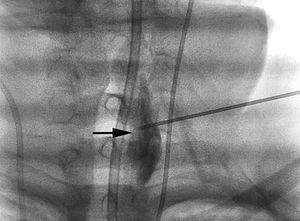

Las siguientes 48 h se caracterizaron por episodios fluctuantes de focalidad izquierda y evidencia de vasoespasmo grave por Doppler transcraneal (DTC), con velocidades medias de hasta 250cm/s en la ACM izquierda e índice de Lindegaard superior a 3. Al tercer día, se repitió la angiografía con nueva infusión de 8mg de nimodipino, esta vez con resultado parcial. La tomografía computarizada realizada posteriormente mostró una pequeña lesión isquémica frontal izquierda. Debido a la ausencia de mejoría clínica (plejía del brazo derecho y disfasia), se contactó con la Unidad del Dolor para la realización de un bloqueo del ganglio estrellado cervical izquierdo, que se llevó a cabo al cuarto día de ingreso bajo control de escopia (fig. 1). Se administraron 10ml de bupivacaína al 0,5% en bolo y se dejó colocado un catéter para la administración repetida del fármaco cada 12 h. A los 30 min del bloqueo, se objetivó recuperación parcial de la fuerza en el brazo derecho, mejorando la nominación de objetos. En ese momento, el DTC mostró una disminución de la velocidad media en ACM izquierda del 10% (fig. 2 A y B), que descendió de forma progresiva en las siguientes horas. Después de 3 días de tratamiento con bupivacaína (6 dosis), la paciente mantuvo una mínima claudicación braquial, sin alteraciones del lenguaje, consiguiendo la retirada del bloqueo cervical sin recidiva de los síntomas y con descenso de la velocidad por DTC hasta del 70% con respecto a su valor máximo.